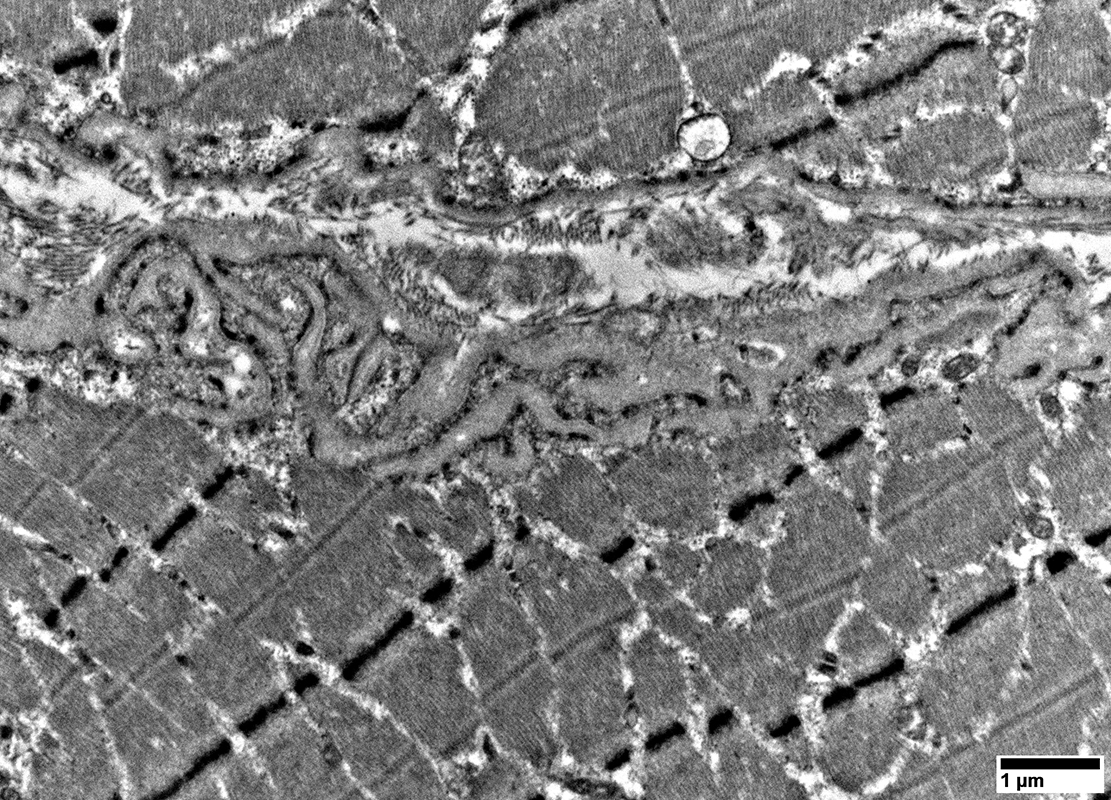

Mitochondrial proliferation between sarcomeres

From: R Schmidt

Mitochondrial proliferation & enlargement: Beneath muscle fiber surface